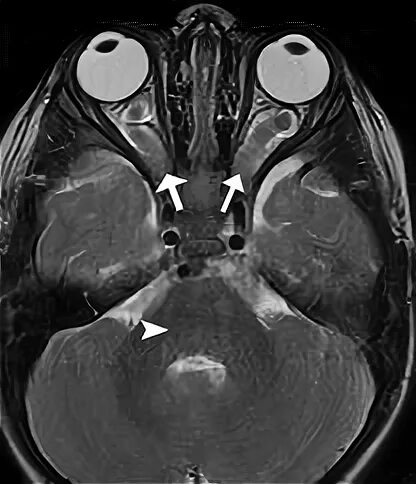

Мрт орбит и зрительных нервов